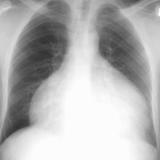

Mitral Valve Disease

Album: Mitral Valve Disease

Date: 03/17/2004

Size: 30 items

Views: 37492